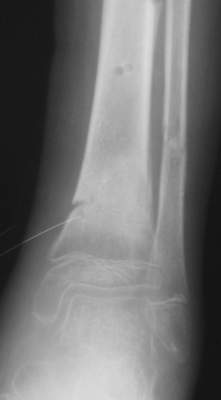

Промежуточный

A> Операции: 1 Клиновидная резекция на вершине деформации м\берцовой кости.

A> 2 Тугоподвижный ложный сустав н\3 б\берцовой кости.

Т.е. на фоне некоторого наверняка имевшегося укорочения голени

произвели ее дополнительное укорочение?

Или как?

A> Спицы удалены через 1,5 недели после операции.

A> Особого смысла в них не было.

Есть даже тень периостальной костной мозоли и сросшийся перелом

малоберцовой кости.

Это сросшийся перелом малоберцовой кости. И ложный сустав

н\3 б\берцовой кости.